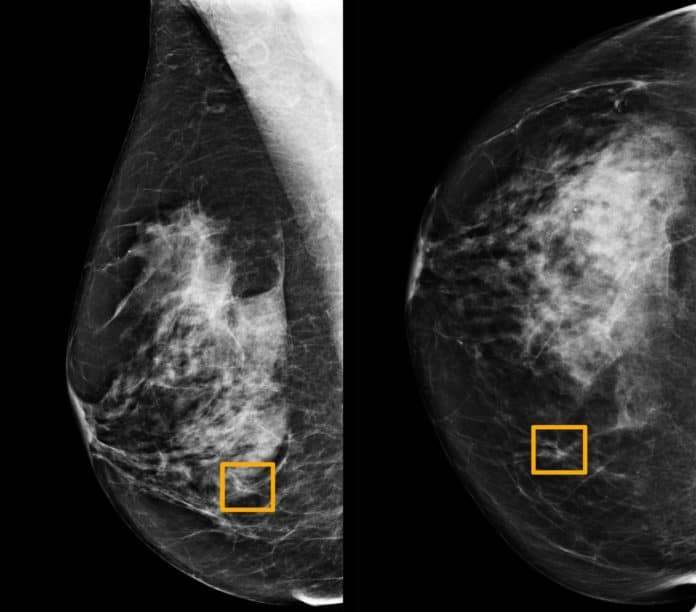

Telset.id, Jakarta  – Ahli radiologi menyebut, sistem kecerdasan buatan atau artificial intelligence atau AI Google bisa membantu deteksi kanker payudara lewat screening mammogram. Bahkan, akurasinya dinilai sangat tinggi.

Seperti dilansir Reuters, dalam studi yang diterbitkan di jurnal Nature pada Rabu (1/1/2020) waktu setempat, AI Google memiliki potensi untuk meningkatkan akurasi skrining kanker payudara yang diidap oleh banyak perempuan.

Mereka kemudian membandingkan kinerja sistem dengan hasil aktual dari 25.856 mammogram di Inggris dan 3.097 di Amerika Serikat. Studi menunjukkan, sistem AI dapat mengidentifikasi kanker dengan tingkat akurasi tinggi.

Keakurasiannya sama dengan ahli radiologi. Fakta tersebut membantu mengurangi jumlah hasil positif palsu sebesar 5,7 persen untuk kelompok berbasis di Amerika Serikat dan 1,2 persen untuk kelompok berbasis di Inggris. [SN/HBS]